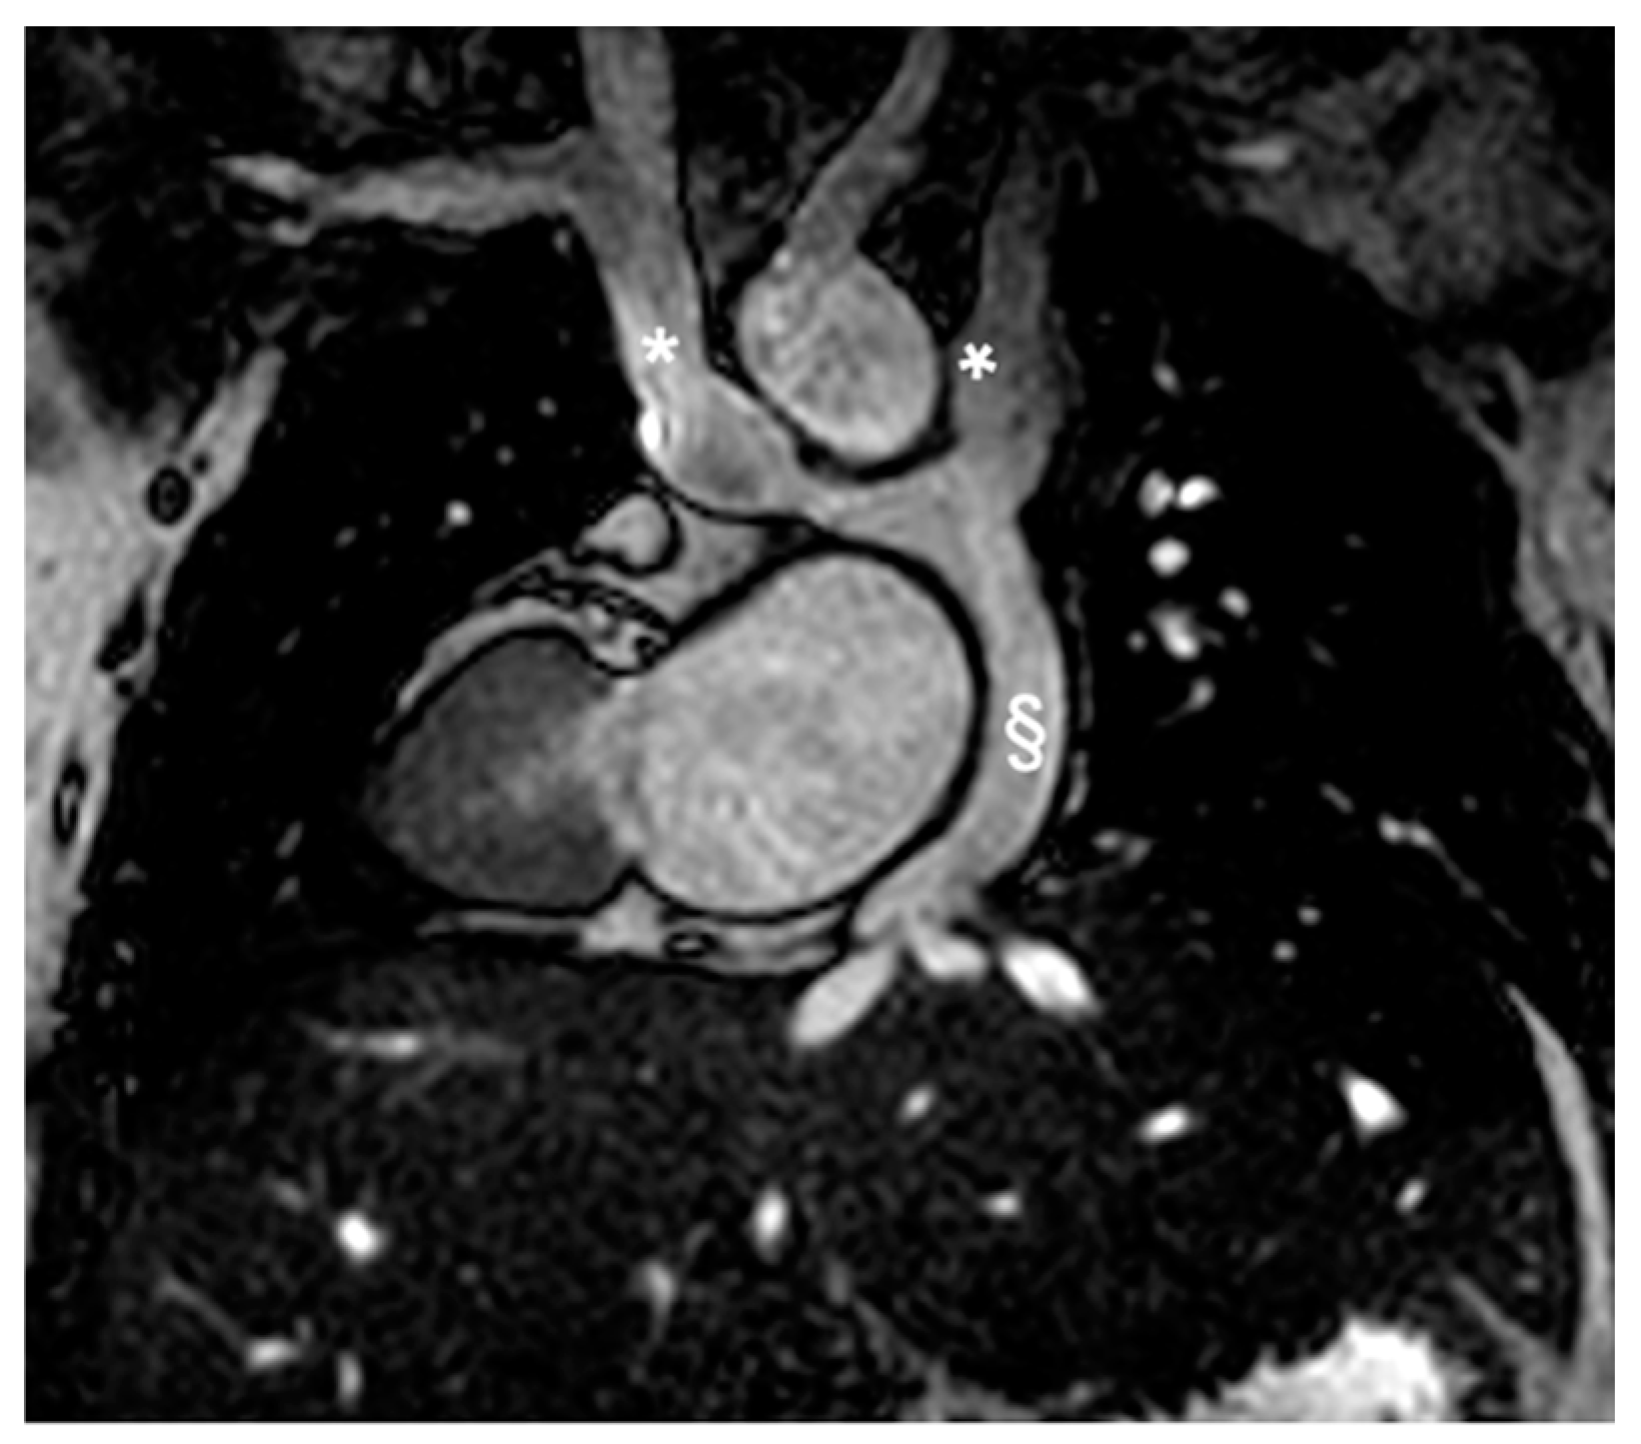

2.2.2. Congenitally Corrected Transposition of Great Arteries (cc-TGA)

2.2.3. Tetralogy of Fallot